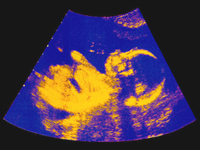

Ребенок в утробе матери. Ультразвук